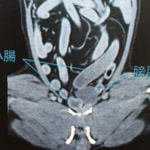

■症例5 11歳 未去勢雄 パピヨン

排便が困難になり始め、食欲が低下してきたとの主訴で来院。直腸検査にて直腸左側に宿便が貯留している憩室を認めた。

用手による摘便処置、緩下剤の内服と食餌療法をスタートしたが、排便困難が続いた為、会陰ヘルニア整復術実施に至った。

両側会陰ヘルニアを内閉鎖筋フラップ法にて整復し、直腸腹壁固定と去勢手術を同時に実施した。

術後、排便はスムーズになり食欲も安定し、経過は順調である。